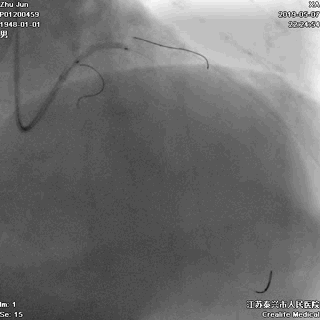

前降支至左主干行PTCA

前降支植入第一枚STENT

前降支-左主干STENT定位和植入